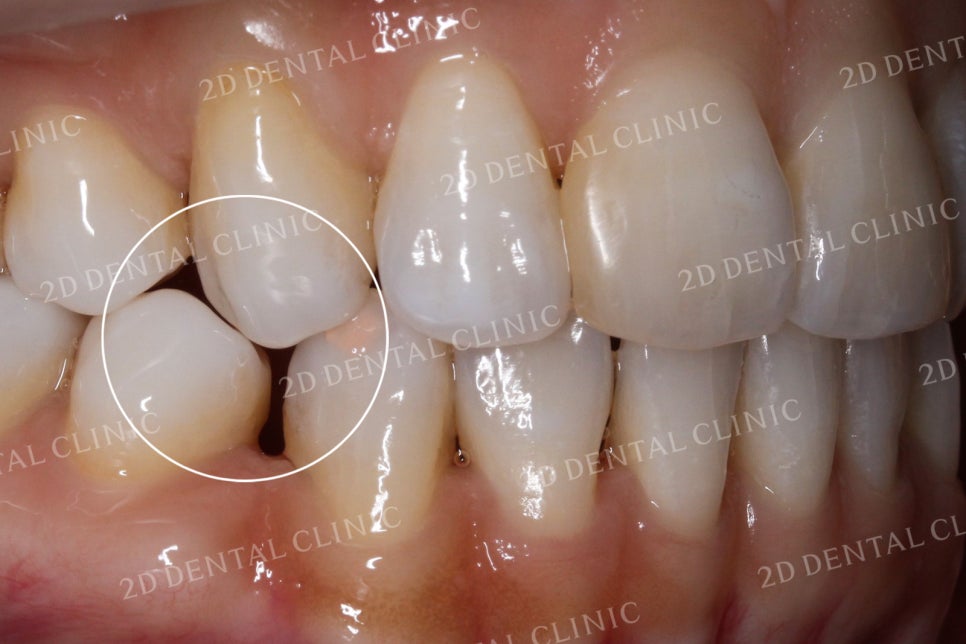

구치부의 치아 또한 틈새가 크게 생겨난 모습입니다.

벌어진 치아는 여러가지 치과치료로 수복할 수 있습니다.

그 중 쎄라필름과 같은 심미보철치료는 교정과 같은 치과치료가 가진

시간적 한계를 뛰어넘는 치료 방법입니다. 만약 이러한 심미치료가 필요하시다면

개인의 치아와 구강 환경을 전문가와 상의 후 적합한 방식으로 진행하시기 바랍니다.